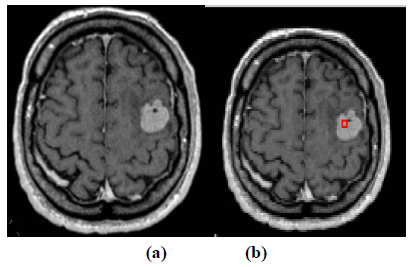

The experiment is conducted using brain web and Digital Imaging Communications in Medicine (DICOM) database [27, 28]. These database consists of T2 weighted MR images of sizes with tumor history. Pre-processing of an original MR image is an important step before applying the segmentation algorithms. In this case, the original MR image is pre-processed by applying median filter. Median filter removes salt and pepper noise which is very common in MR images of the brain. After removing the noise, wavelet transform is applied for multiresolution analysis to enhance the features of the image. Then, spatial FCM technique is applied to the multiresolution image. This technique minimizes search area to a very small region by creating cluster number k parameter for termination and max iteration values. Finally, these tumor clusters are segmented by level set evolution algorithm [29-39]. The following experimental results demonstrate the segmentation process used in the proposed methodology. In this experiment, two MR images having tumor in different locations of the image were selected to test the proposed segmentation algorithm. In Fig. (3), the original image and contour initialization for MR image 1 is shown. The contour evolution and final segmentation are depicted in Fig. (4). Similarly, Fig. (5) shows the original MR image 2 and the initial contour position. As the iteration values increases, the contour evolves towards the tumor boundary.